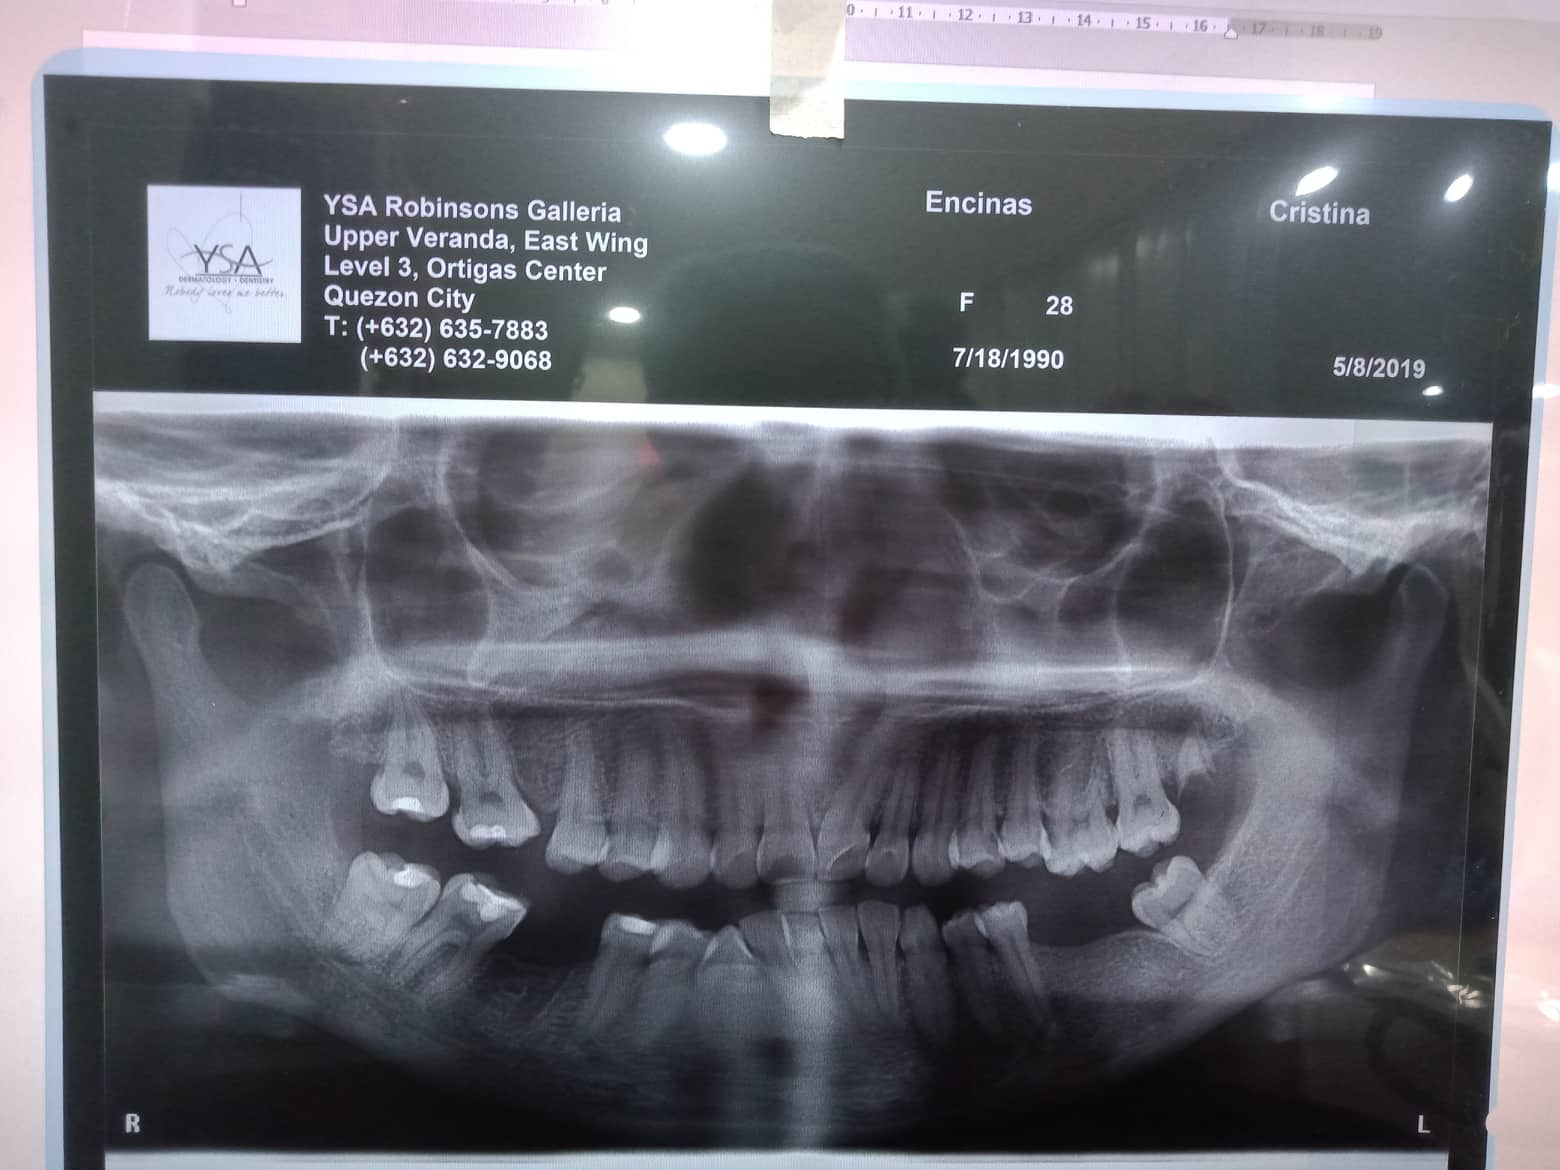

Edit Record Check our patient data records. Add patient information Patient Info Profile picture Last Name First Name Middle Name Birthdate Age Street Barangay City Country Zip Code Contact number Email Procedure 10/16/21 adj 16*22U/L extrude 44- chipmunk double elastic chain and power o upper to left 12/16/21 - chain upper/ 16*22 uL ss s-elastic 44 to 13, 45 to 14- chipmunk 1/25/22- s elastic on right q/ box elastic R Quad- fox. R quadrant n 16 niti 02/11/22- chipmunk s elastic- 13 to 44/ 14 to 45- same wire 3/18/22-chipmunk 13-44/ 14-45/ rabbit elastic box- 23-24 to 33-34/ 16x16 niti lower 05/13/22 13-14 to 43- chpmnk 16x16 ss L 6/18/22- Month Of September For Removal / same wire/ 44 extrude- chipmnk 7/29/22- U same wire placed echain; L 016x022 SS close ligation; Pt concern abt midline deviation on upper arch, told her that if she wants to address the concern, she may opt for TADS, however it is time consuming and may extend her ortho tx. 8/23/22- Same wire U, stripping on 22D and 23M, Chain U, Penguin 13-33 9/27/22 - removal of braces - upper and lower impression for retainers. File 302450901_408871331368693_864463967539202601_n.jpg File 2 302318849_520060069884290_5536848649181119832_n.jpg File 3 302487020_441958927896332_8414292300474769290_n.jpg File 4 304829205_492469312712272_6122418120013648735_n.jpg File 5 File 6 File 7 File 8 File 9 File 10 File 11 File 12 File 13 File 14 File 15 File 16 File 17 File 18 File 19 File 20 Retain Record Retain Record Yes No Save Your Changes